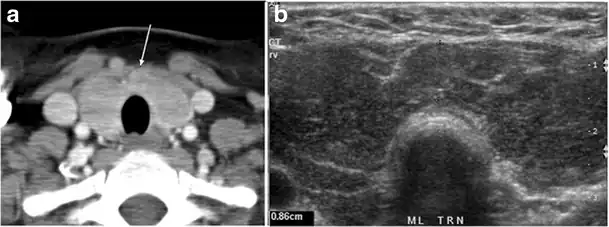

Fig. 7. A 51-year-old female patient post total thyroidectomy for PTC with elevated thyroglobulin measurement. an Axial non-enhanced CT scan of the neck at the level of the thyroid bed demonstrates a well-defined, rounded, homogenously dense soft tissue situated between the trachea and left internal jugular vein (white arrow). b Transverse ultrasound image of the neck demonstrates a well-defined, homogeneous, hypoechoic soft tissue nodule measuring 6 mm (white arrow) with no detected micro-calcifications. Biopsy showed a predominantly residual normal thyroid tissue with micro-foci of PTC.[1] -